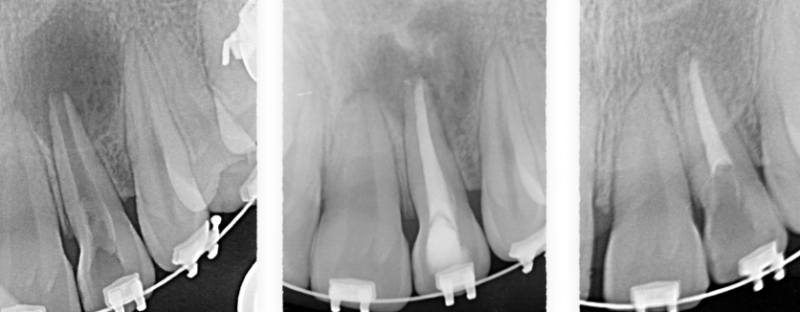

La cirugía endodóntica se puede usar para localizar fracturas o canales ocultos que no aparecen en las radiografías pero que aún manifiestan dolor en el diente. Las superficies radiculares dañadas o el hueso circundante también pueden tratarse con este procedimiento.

Se hace una incisión en el tejido de las encías para exponer el hueso y el tejido inflamado circundante. El tejido dañado se elimina junto con el extremo de la punta de la raíz. Se coloca un relleno en el extremo de la raíz para evitar la reinfección de la raíz y se sutura la encía.